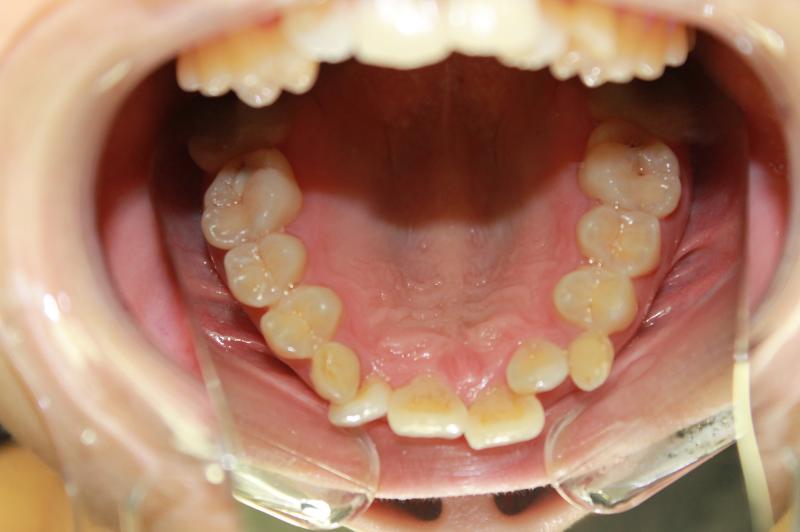

INVISALIGN - 13 months, 1 lower tooth removal, 1 series of aligners to align teeth and create the proper amount of space for 2 cantilever bridge to replace congenitally missing cuspids. COSMETIC DENTISTRY - 2 porcelain cantilever bridges and cosmetic bonding to reshape incisors and close gingival spaces. TOTAL TREATMENT TIME, 15 months

Cosmetic Dentistry, Mid-line Asymetry, Missing Teeth, Severe Crowding